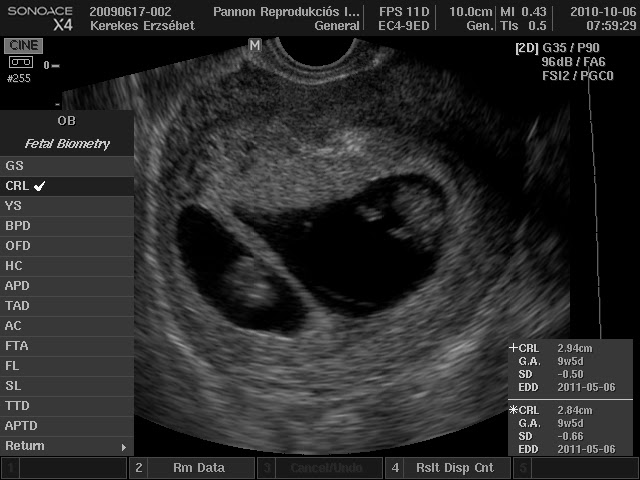

7 hetes terhesség petezsák mérete. Az ultrahangos vizsgálat során a petezsákot meglétét keresik a terhesség nagyon korai szakaszában ez mutatja meg hogy a teherbeesés megtörtént. Hetében baba tovább fejlődik és már eléri a 1 1 2 cm nagyságot. Az utrusban szabályos 16x16mm petezsák. 1 7mm 3 1mm 4 5mm a 7 hetes embrió mérete.

A 7 hetes embrió mérete. A uh s papírra azt írták hogy 6 hetes. Az embrió mérete crl 6 hetes terhességben 4mm 8 hetesen 17mm 10 hetesen 34mm körül van. 7 hetes terhesen a 29 6 mm petezsák.